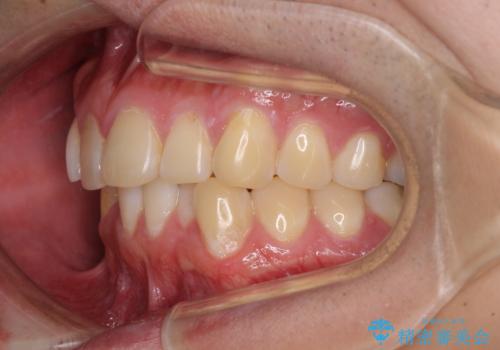

- 上下前歯のデコボコを気にして来院された患者様です。

前歯のデコボコ以外に左側の奥歯の咬み合わせに問題がありましたが、価格を抑え、短期間で気になる前歯を治したいとのことでした。

写真より左側臼歯の咬合がタイトではないことが分かりますが、こちらは保定期間に徐々に咬合させていくこととしました。